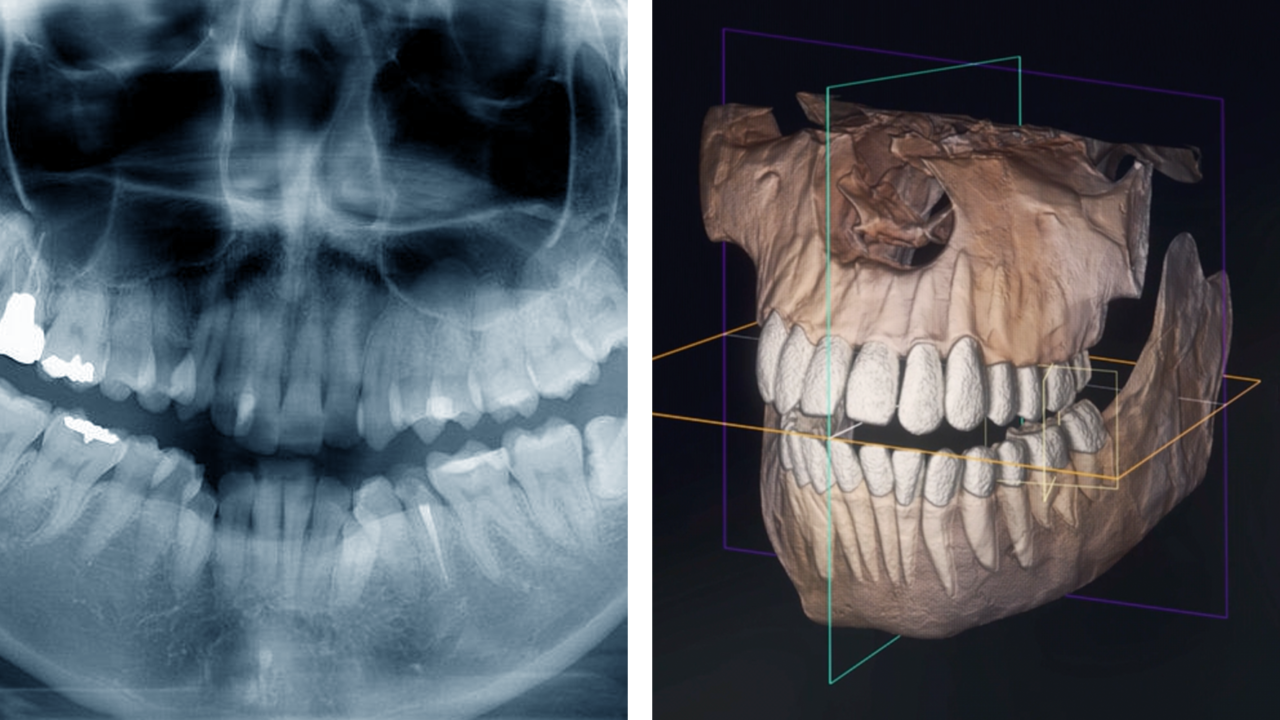

歯科用CTで検査してくれるか

院内に歯科用CTのない経験不足の歯科医師は、レントゲンの撮影だけで済ましてしまいがち。

CT撮影を行わずに治療を進めるケースが少なくありませんが、これが矯正治療に失敗する理由の一つ。

当院含め、矯正を専門に手がける経験豊富な歯科医師は、必要に応じて歯科用CTでの3次元診断を行います。

2次元レントゲンではわからない、骨の厚みや顎の幅、歯根の正確な長さ、顎関節の形状を三次元で見ながら診断することで、より安全で正確な治療計画を立てられるのです。